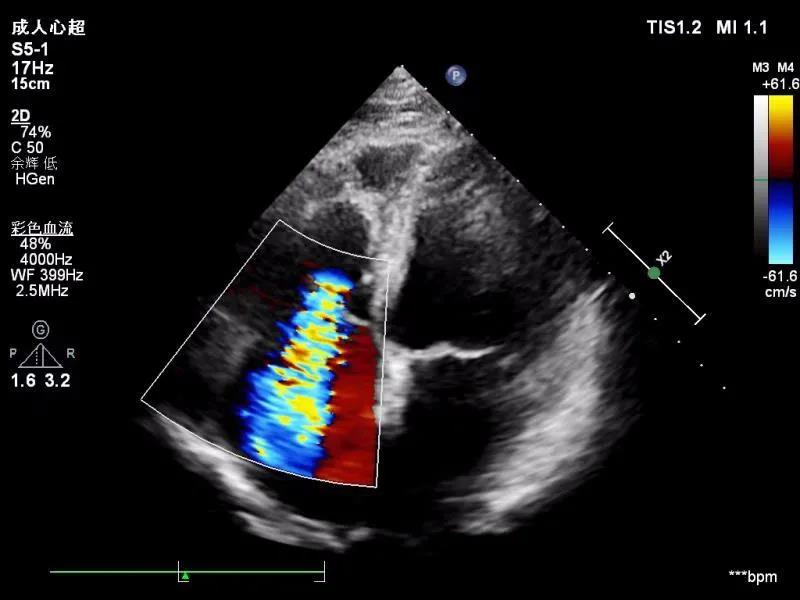

很多人会就此产生疑问:我做的是彩超检查,为什么拿到的检查单看着还像是黑白的?事实上,彩超虽然姓“彩”,但并非像彩色电视机一样进行实时全彩色的呈现。彩超的全名是彩色多普勒超声,彩超是在B超的基础上增加了彩色多普勒技术,B超是超声的基础显影,是辉度成像,出现的图像接近于黑白色,辉度的英文brightness的字头是B ,临床简称B超,过去超声的确是B超,就像黑白电视机一样,随着技术发展目前各医疗机构都是彩色超声,就像家家都是彩色电视机一样。彩超在B超的技术上增加了血流图,对运动的脏器或红细胞的反射(散射)波频信号进行彩色编码和检测处理,以红色表示朝向探头运动,蓝色表示背离探头运动,然后叠加到B型超声图像上,获得彩色超声。

彩超能快速直观显示血流的二维平面分布状态、血流的运行方向、时相、速度、性质等,在血管方面可辨别动脉和静脉,识别血管病变。在心脏方面可明确心脏瓣膜是否狭窄及关闭不全,是否存在异常的分流信号。